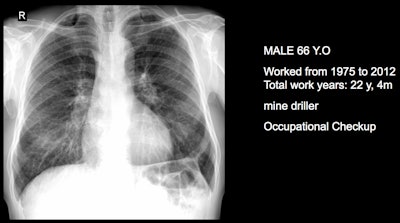

Three clinical cases courtesy of Dr. Luis Antonio Campos Calderon.

The International Labor Organization (ILO) International Classification of Radiographs of Pneumoconioses is used for epidemiological studies, screening, and surveillance of workers exposed to dust in the workplace, and clinical purposes, and the National Institute for Occupational Safety and Health (NIOSH) B Reader Program certifies physicians in the ILO classification system. Each case should discuss its ILO classification and brief comments about the workflow, he noted.

"Pneumoconiosis often develops slowly, and symptoms may not appear until significant damage has occurred. Early detection is crucial but can be difficult due to limited resources and awareness," Campos explained. "This diagnosis can be fraught because in Peru workers diagnosed with pneumoconiosis have rights to compensation and healthcare under current labor laws and social security systems. However, navigating the legal and bureaucratic processes to claim these benefits can be complex and challenging."

The main diagnostic criteria are: Work history (minimum 10 years exposure to silica dust or other particles); chest x-ray (micronodular pulmonary fibrosis, coded according to ILO classification); progression (image profusion increases over time, even after exposure cessation; irreversibility (disease is progressive and irreversible, no stable pneumoconiosis over time).